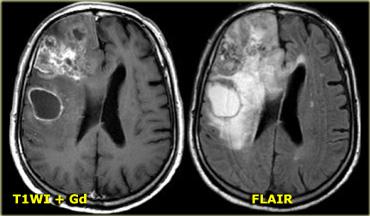

U nguyên bào đa dạng (GBM) với ngấm thuốc không đồng nhất và thành phần nang với ngấm thuốc dạng vòng

Bên trái là ví dụ về u nguyên bào đa dạng (GBM).

Sự ngấm thuốc cho thấy đây là khối u độ cao, nhưng chỉ một phần của khối u ngấm thuốc.

Lưu ý rằng còn có một thành phần nang với ngấm thuốc dạng vòng.

Các tế bào u có thể lan rộng vượt ra ngoài vùng phù não như thấy trên ảnh FLAIR.

Điều này là do u thần kinh đệm phát triển thâm nhiễm vào nhu mô não bình thường – ban đầu không có bất kỳ thay đổi tín hiệu MRI nào.

Bên trái là hình ảnh của một khối u nằm ở bán cầu não phải.

Mặc dù là khối u lớn nhưng hiệu ứng khối còn hạn chế.

Điều này cho thấy có sự phát triển thâm nhiễm rõ rệt, đặc điểm điển hình của u thần kinh đệm.

Lưu ý tính không đồng nhất trên cả chuỗi xung T2W và FLAIR.

Có ngấm thuốc không đồng nhất dạng đốm.

Tất cả các đặc điểm này điển hình cho GBM.

Hầu như không có khối u nào khác có biểu hiện tương tự như vậy.